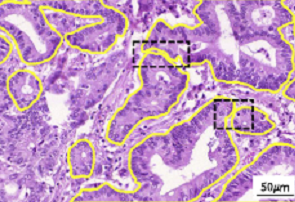

In the last few decades, the advent of computational pathology has catalyzed the advancements in clinical diagnosis, expedited development of new interactive models for pathology education and paved way for incredible rise in whole slide image analysis tools. It has revolutionized the entire tissue specimen analysis process for pathologists. From manually analyzing thousands of tissue slides via microscope requiring specialized doctors to automatic digital slide generation via scanning and using AI based deep learning techniques has spawned fatal disease diagnosis such as cancer using image analysis. In digital pathology nuclei and gland instance segmentation in whole slide images is of pivotal value for abnormality assessment. It plays a key role in histopathological image analyses whether it be identification of major chronic disease including tumor localization through segmentation or classification as benign or malignant. Glands are often considered as one of the main histological structures present in most of the organs as primary mechanism for proteins and carbohydrates secretion. However, it has been observed that adenocarcinomas, regarded as the most severe type of cancer, originates from glandular epithelium as malignant tumors. In figure 1, left patch shows histopathological image of a colon tissue stained with routinely used Haematoxylin and Eosin technique while right patch is individual gland of a colon tissue with sub structures. This makes understanding of glands morphology a pivotal step for assigning degree of malignancy of major adenocarcinomas e.g in breast, colon, lung and prostate. Thus accurate gland instance segmentation is considered as a necessary step for obtaining valid morphology information.

However, nuclei and glands instance segmentation cannot be regarded as a simple task for non experts in pathology labs. Despite being continuous advancements in learning algorithm, nuclei segmentation is still an extremely challenging task because of blurred nuclei boundaries, differences in size and shape highlighted by Vahadane et al. [12], uneven staining, pathological changes on pathological images, morphological abnormalities [13] and substantial color variations described by Rashmi et al. [14]. Similarly, varying morphology of glands at different histological grades, different intrinsic features of glands WSIs poses major challenge during segmentation of instances. Firstly, applying mathematical shape model for instance segmentation gets difficult due to shapes heterogeneity. Figure 2 shows structural variations of nuclei in different organs. Secondly granule filled cytoplasm cause nucleus extrusion to flat shapes as compared to oval or round structures in normal cases mentioned by Yan et al. [15]. Thirdly, cellular matrix variations results in anisochromasia thus resulting in additive noise in background compared to normal intensity gradients.